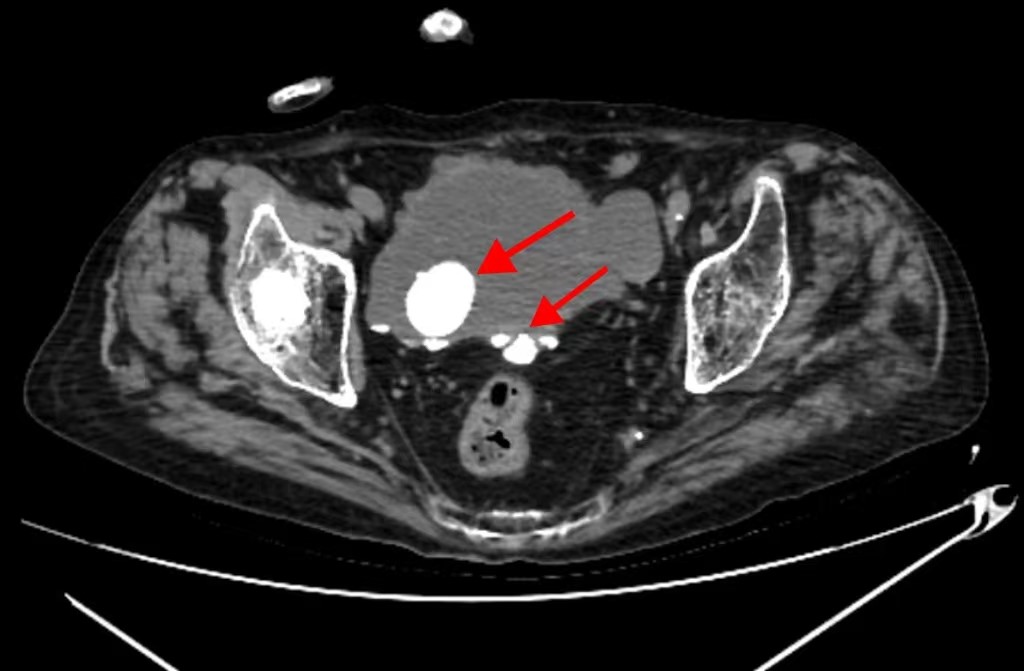

患者杨大爷因“排尿困难1周”入院,同时还伴有腰痛、血尿等症状。术前CT检查提示病情复杂:不仅存在右侧输尿管结石、膀胱多发结石与憩室、前列腺增生,还伴有右肺可疑癌变、冠心病。此外,患者有食管癌根治术手术史、腰椎及髋关节手术史等,叠加患者高龄,令治疗难度增大。

经过周密的术前准备,在麻醉手术科李健主任医师团队的全程护航下,沈罡主任医师主刀,手术团队依序攻克了三重梗阻:先是向上处理源头,利用输尿管镜精准定位并粉碎了右侧输尿管的结石,解除了肾脏积水的风险;继而通过膀胱镜将膀胱内多枚结石击碎并取出,其中最大直径超过3cm;最后运用经尿道前列腺等离子切除术,将增生的前列腺组织精准剜除,从根本上拓宽了排尿的最终出口。整台手术一气呵成,实现了从输尿管到膀胱、再到前列腺的全程疏通,为患者一次性扫清了泌尿通路上的障碍。